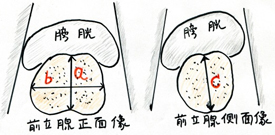

また前立腺のおおよその大きさ・形状と合わせて残尿をみるにはエコー検査が極めて有用です。尿を十分に溜めた状態で恥骨上にプローベを当てれば(高度の肥満症例でない限り)、前立腺の形状を概ね理解することができますし、時には膀胱内病変(腫瘍や結石)の診断にも有用です。また排尿後には残尿も測定可能でありこれにより大まかな排尿状態の理解が可能となります。前立腺体積、残容量ともに3方向を計測し0.55を乗ずることで回転楕円体に近似した体積が測定できます。薬剤治療にもかかわらず症状の改善されない方、あるいは前立腺体積が30ml以上、残尿が50ml以上が続くような場合は一度は泌尿器科の診察を受けられるのがよいかと存じます。体積の測定は3方向を測定し a x b x c x 0.55cm3 で計算する。(図の残尿であれば6.5 x 4.5 x 3.5 x 0.55=65.3ml)

前立腺の形状の理解と体積測定